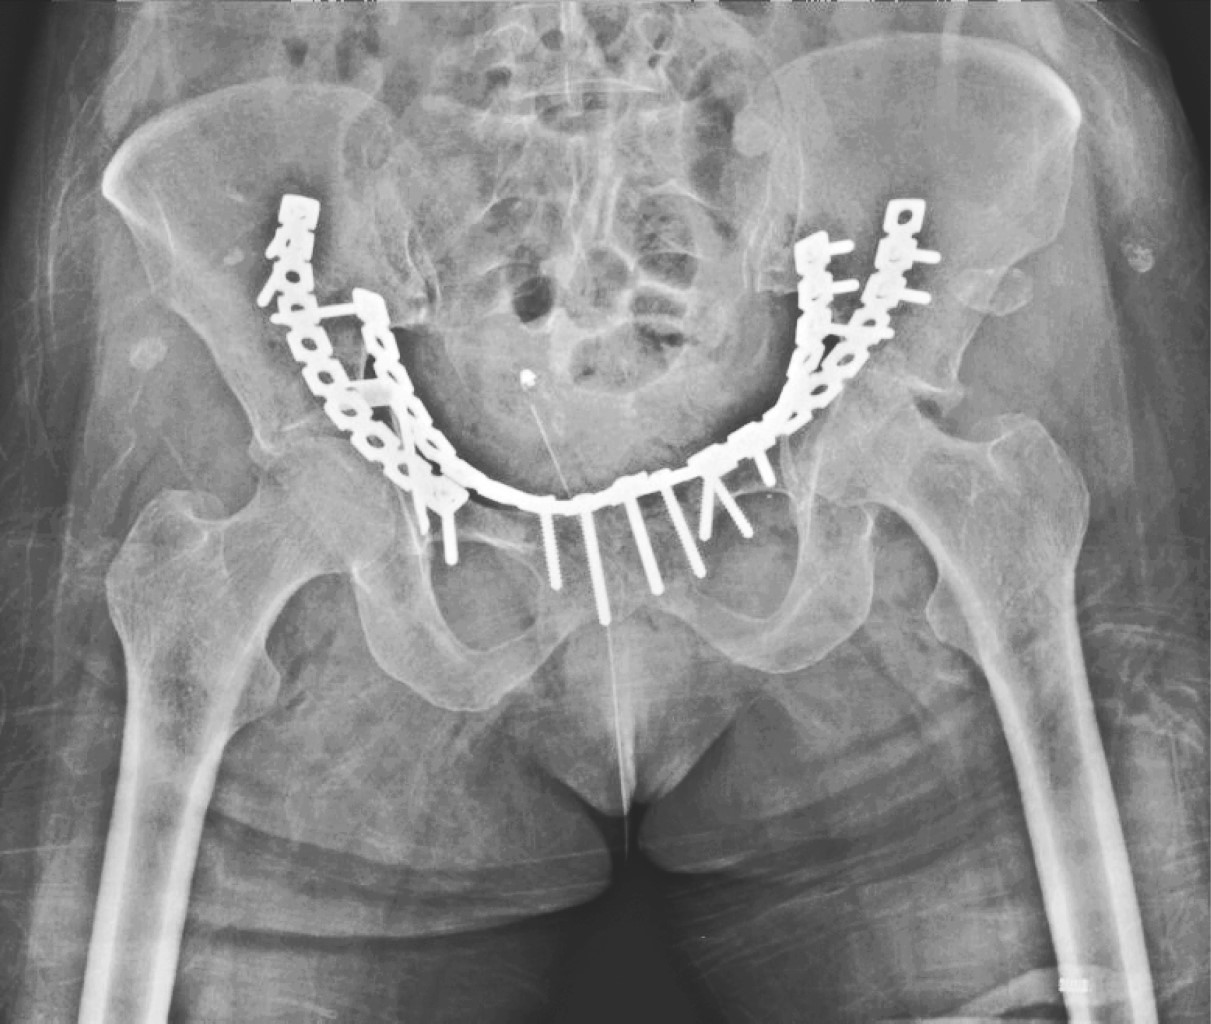

Bilateral acetabular fracture secondary to seizure. Case report and literature review

Introduction: acetabular fractures are generally related to high energy mechanisms. A case report and literature review are exposed. There are few publications with reports of bilateral acetabular fractures secondary to seizures, a total of 26 case reports, no citations in the Mexican population. Objective: to present a case of bilateral fracture of the acetabulum associated with convulsive crises, its management and clinical evolution. As well as a review of the literature and injury mechanims. Clinical case: a 68-year-old female patient who debuted with an episode of seizures, presenting with a bilateral fracture of the AO acetabulum type 62B3.3/Judet, I. Performing surgical management, through open reduction and internal fixation using a modified Stoppa approach with two plates. 9-hole curved reconstruction plates for the left acetabulum and one open reduction and internal fixation with two 10-hole reconstruction plates and one 6-hole spring plate for the right acetabulum, presenting excellent functional results. Conclusion: the injury mechanims of acetabular fractures continues to be of high energy, with few cases associated with seizures reported in the literature. Inevitably the patient will evolve to a post-traumatic coxarthrosis; the initial management with osteosynthesis and acetabular reconstruction is focused on the future definitive treatment with bilateral total hip arthroplasty with primary components, so far the result is encouraging.

Figure 1